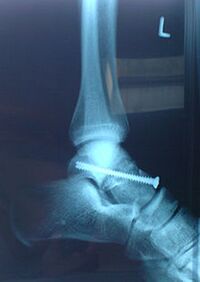

repariertes Sprunggelenk nach Operation (mit Schraube)

Bei Komplettabrissen und in speziellen Fällen ist meist eine Operation notwendig.